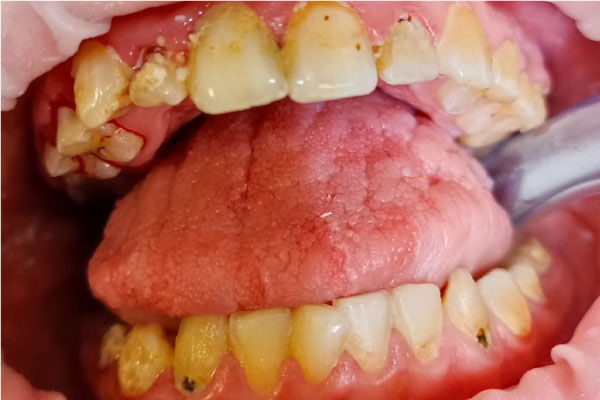

Профилактика: фото До и После

Фото ДО

Фото ПОСЛЕ

Наведите для просмотра

Профессиональная гигиена молочных зубов